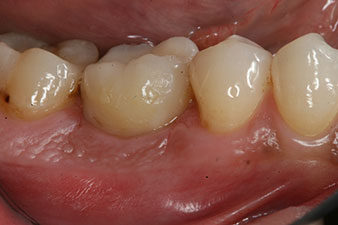

отпечатък

Фиг. 8: Взет е отпечатък за окончателната корона.

Следователно, успешната остеоинтеграция и адекватната биологична стабилност могат да бъдат записани, което даде възможност да се вземе отпечатък в една и съща сесия.

Последните снимки показват закрепената с винт монолитна композитна корона на място и рентгеновата проверка (фиг. 9 и 10) (6).